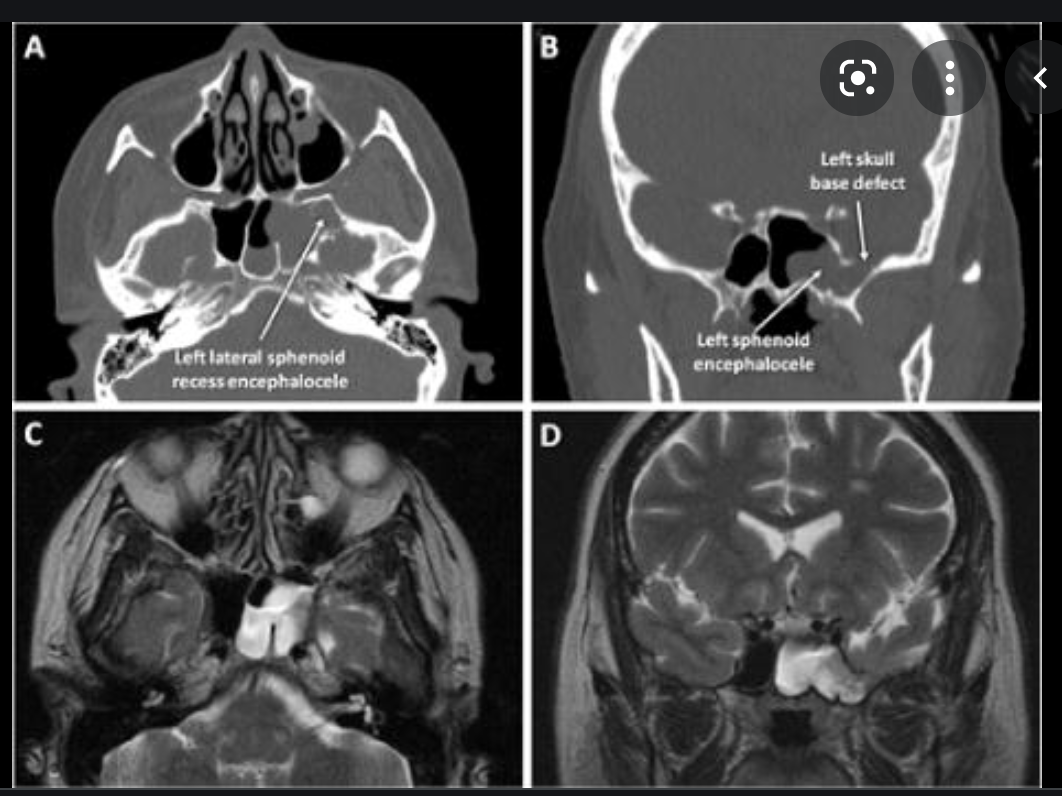

Central skull base Basal cephalocele